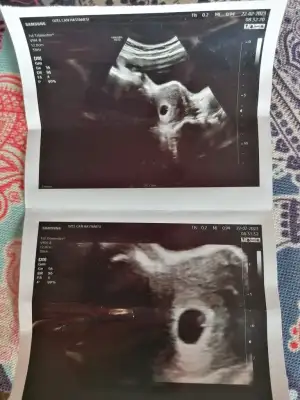

Bizim ilk bebiş daha eşim çok pimpirik hiç kimseye söylememi istemedi ailelere moral olsun dedik söyledik arkadaşlara da sevincimi paylaşayım istedim söyledim 7 kişiye söylemişim aile haricinde hala söylemek istediklerim var da 10-12 hafta olsun öyleBende baya bi soyledim ya